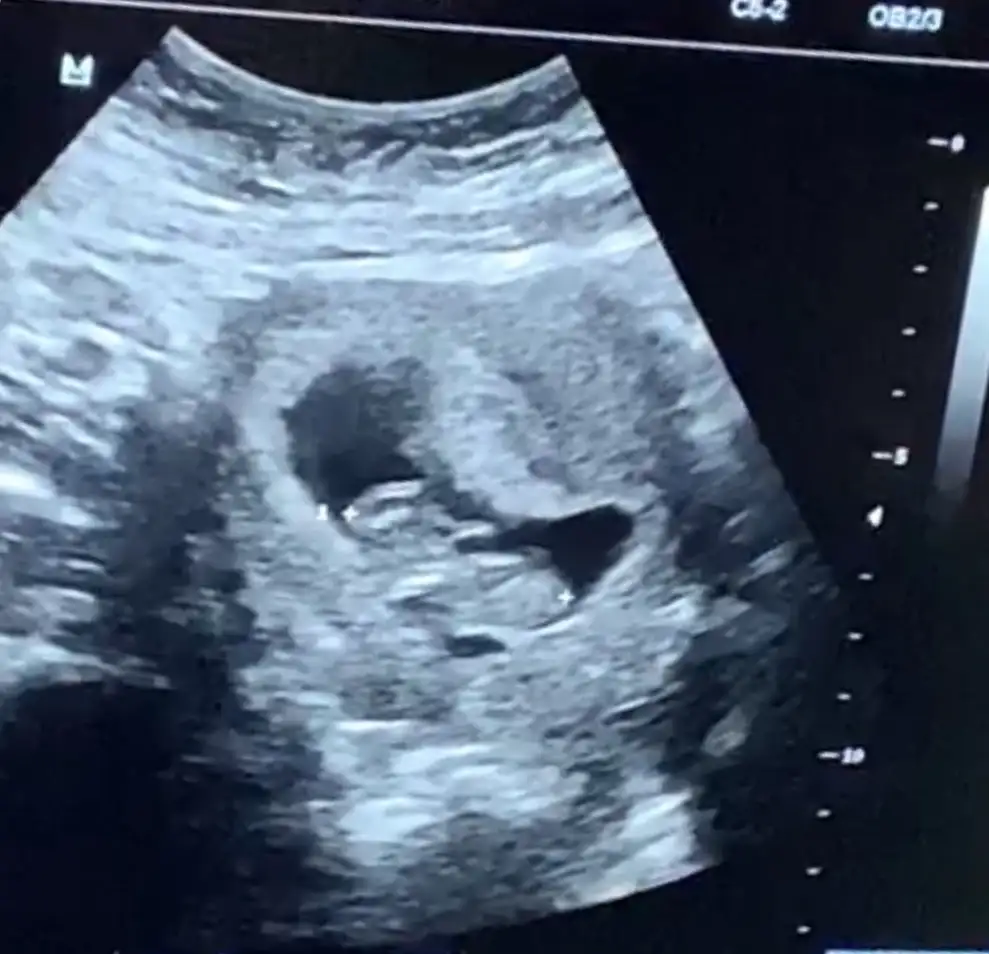

Canim ben sormadim doktora. Ama kahvaltidan 1 saat sonra gittim. Tatli bir sey de yemedim. Ama durmadi yavrum masallah. El salladi bize hep :)) sen de hafif tok git. Cunku olcum alamazlarsa tekrar tekrar gitmek zorunda kaliyormussun. Bilgin olsun.Aa aynı doktora mı gidiyorsun ne güzel :)

Bide tok ac bişey demedimi sanaPircici tok gitmişti kıpır kıpırdı onunkide :)